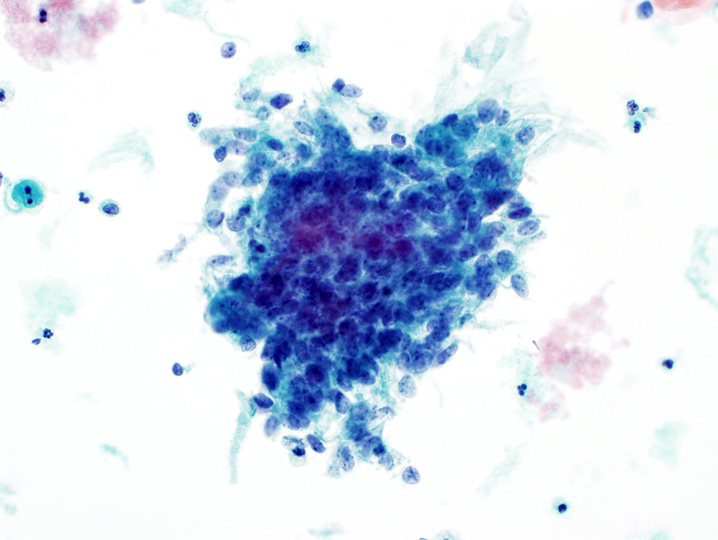

- Endocervical adenocarcinoma in situ (AIS):

- Hyperchromatic nuclei with fine to coarse chromatin

- Nuclear membrane irregularities and notching

- High N:C ratio

- Feathering or rosette formation

Cytology images